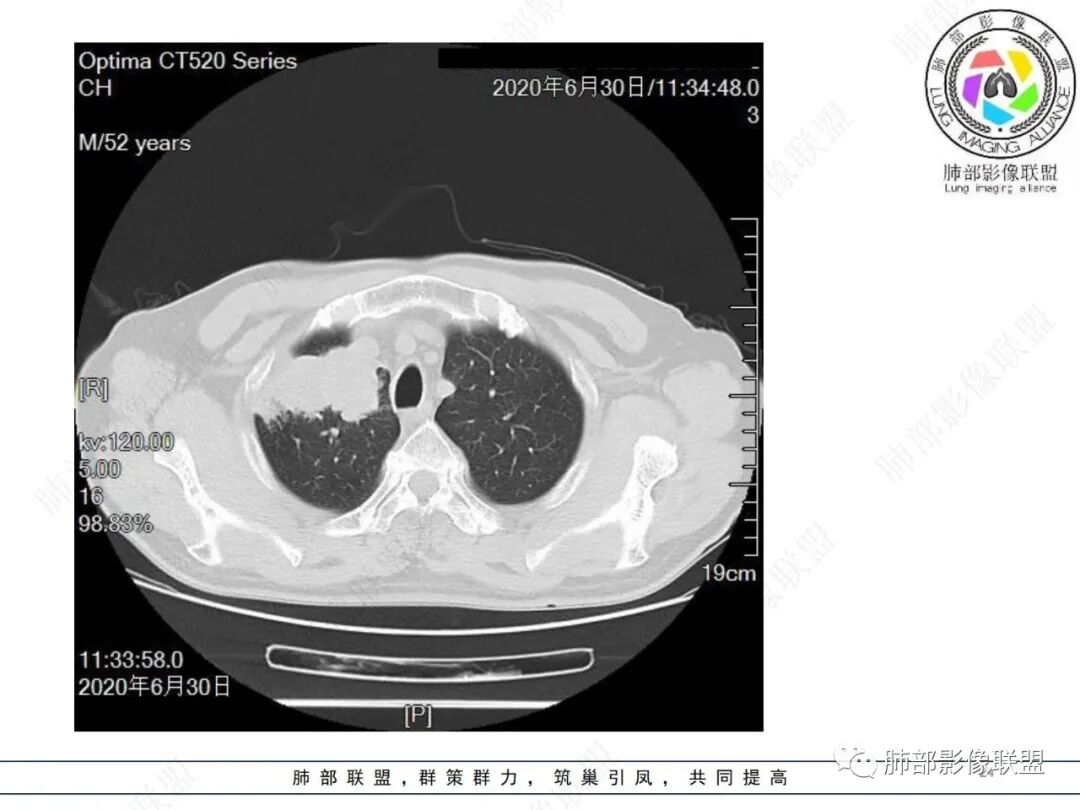

中年男性,有长期吸烟史,右肺上叶不规则肿块,边缘膨隆有分叶,支气管截断,不均匀强化,内有多灶性坏死,癌胚抗原升高,考虑肺癌可能性大,鳞癌可能。鉴别腺癌。

右肺上叶不规则形软组织密度肿块影,边缘见分叶,毛刺,病灶呈宽基底与胸膜相连,病灶内见坏死,增强扫描呈不均匀性强化,右肺上叶支气管截断,纵隔内见肿大淋巴结,肿瘤标志物增高,考虑鳞癌可能,鉴别小细胞癌,腺癌。

老年人,右肺上叶肺不张伴阻塞性炎症,右肺上叶支气管闭塞,增强病灶强化不均匀,可见边缘不清晰的坏死,纵膈淋巴结增大,考虑中央型肺癌,鳞癌可能性大。

右肺上叶不规则肿块,分叶、毛刺,上叶支气管截断,断端圆钝,不均匀强化,其内空泡及坏死,坏死边界不清,考虑腺癌或腺鳞癌,鉴别鳞癌

中年男性,长期吸烟,CT示右肺上叶肿块影,有分叶,毛刺,胸膜牵拉,支气管截断,边缘斑片影,病变内有坏死,强化,淋巴结肿大,首先考虑鳞癌可能性大,鉴别腺鳞癌

右肺上叶占位,支气管阻塞截断,病变周围可见结节及斑片状影,密度不均,坏死边缘不清,纵隔淋巴结肿大,中年男子,吸烟史,考虑鳞癌、腺鳞癌,鉴别结核

除了年龄,吸烟,湖泊样坏死符合鳞癌,其他都不符合,支气管截断,不在肿块中央,远处也没有明显阻塞样改变,更像爬行后截断,肿瘤标志物CEA高得厉害,其他鳞癌标志物并不高。这种坏死,低分化腺癌一样常见,强化远端也有强化,不符合鳞癌,所以我考虑低分化腺癌(伴或不伴有神经内分泌分化)或者肉瘤样癌。

不符合鳞癌有四点:1,截断的支气管不在肿块中央,而是外朝内爬行(肿块外缘大于近端)2、支气管截断在前段,前段远端没有阻塞性改变。3、鳞癌是近端强化,远端为阻塞性的不强化粘液栓或明显强化的不张肺组织,这个是中间坏死,周围强化的肿瘤组织。4、肿瘤标志物CEA增高太明显,鳞癌标志物不高。